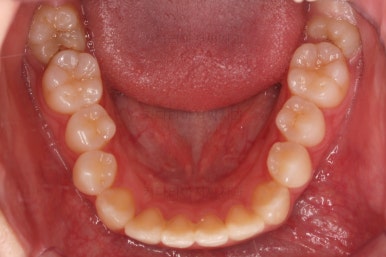

부산교정 키다리아저씨치과에 처음 내원하셨을 당시의 입안 모습과 X-ray 사진입니다.

맨 안쪽 치아가 마치 사랑니인 것처럼 누워있고 애매하게 나와있었어요.

문제는 해당 치아가 썩었다는건데 기울어 있는 치아를 제대로 치료할 방법은 사실상 없죠. 앞에 치아에 가려진 부분이 썩었으니깐요.

저대로 계속 놔두게 되면 누워있는 어금니 + 앞쪽 어금니 두 개가 다 상해서 결국 뽑아야 되는 상황까지 벌어질 수 있어요. 그것도 양쪽으로 모두 다 요.

약간의 주걱턱 느낌에 약간의 돌출감, 전반적인 치열의 가지런한 느낌은 나쁘진 않았지만 약간의 불량한 교합상태였어요.